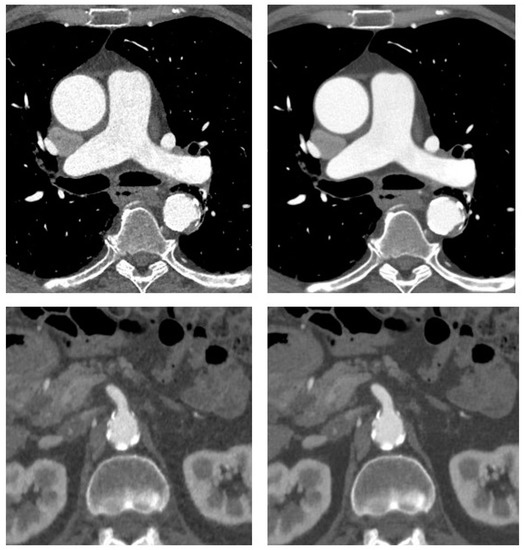

| Obese Patients (n = 17) | Normal-Weight Patients (n = 17) | |||||

|---|---|---|---|---|---|---|

| Contrast-to-Noise-Ratio | ASIR-V | DLIR | p-Value | ASIR-V | DLIR | p-Value |

| Ascending Aorta | 7 (6–8) | 14 (12–16) | <0.0001 | 8 (8–9) | 19 (15–22) | <0.0001 |

| Thoracic descending aorta | 7 (6–7) | 13 (11–15) | <0.0001 | 8 (7–9) | 18 (13–19) | <0.0001 |

| Abdominal aorta | 12 (8–13) | 19 (15–24) | <0.0001 | 9 (7–12) | 16 (11–21) | <0.0001 |

| Iliac arteries | 14 (12–15) | 21 (19–25) | <0.0001 | 15 (13–16) | 24 (19–28) | 0.001 |